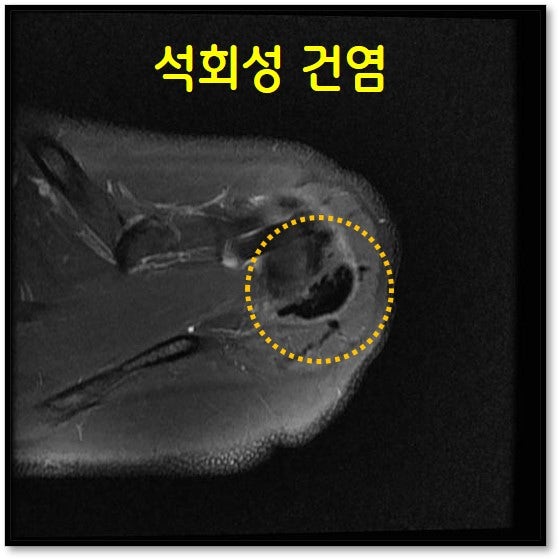

MRI 상 극하근 상부에 커다란 석회가 있는 것이 관찰됩니다.

환자께 뉴핌스치료 (석회분쇄흡입술) 을 권고하 드렸습니다. 부위마취를 한 후 환자분은 통증이 없는 상태에서 뉴핌스 치료 (석회분쇄흡입술) 를 시행하였습니다.